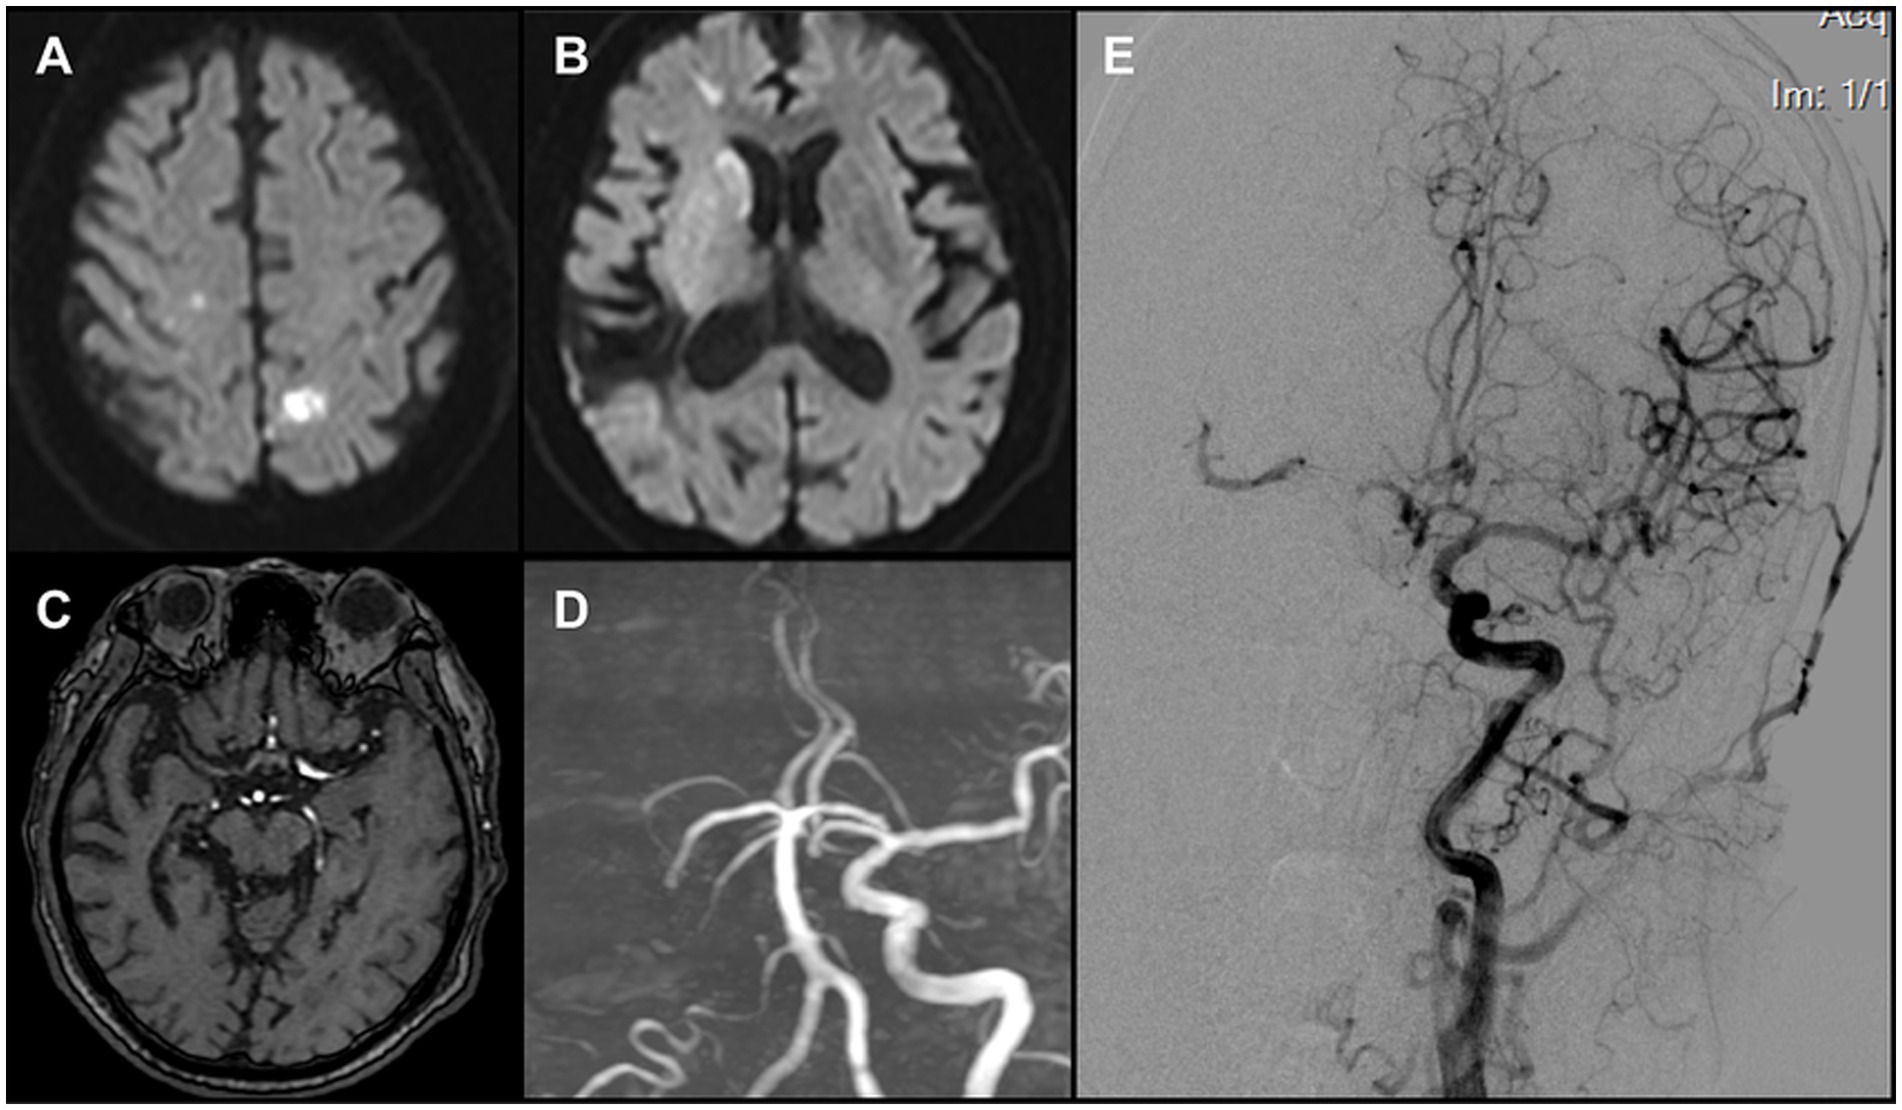

Emergency MRI at 07:50 demonstrated multiple acute infarcts in the right caudate head and bilateral frontal and parietal cortices (Figures 1A,B). MRA did not visualize the right ICA or MCA (Figures 1C,D). A diagnosis of acute large-vessel occlusion ischemic stroke was made. Given the patient’s long-standing atrial fibrillation, the TOAST classification suggested a cardioembolic etiology. In this context, the occlusion was considered most likely at the ICA terminus. Because of the mismatch between infarct volume and clinical deficit, the case fulfilled DAWN trial criteria for mechanical thrombectomy. Consent for urgent endovascular intervention was obtained from the patient’s family.

Figure 1. (A,B) DWI revealed multiple acute infarcts involving the right caudate head and the bilateral frontal and parietal cortices. (C) Original MRA images demonstrated non-visualization of the right middle cerebral artery (MCA). (D) TOF 3D reconstruction demonstrated non-visualization of the right internal carotid artery (ICA) and the right MCA (E) Left carotid angiography indicated a patent anterior communicating artery. A thrombus was identified in the proximal right MCA, causing subtotal occlusion, while compensatory flow to the MCA territory was provided by the collateral circulation.

2.2 Procedure initiation and FFT identification

The patient arrived in the angiography suite at 08:30, and an 8F sheath was introduced via the right femoral artery. Using a multipurpose diagnostic catheter, a Neuron MAX 088 guiding catheter (Penumbra, USA) was advanced into the left CCA. Angiography demonstrated a patent left ICA with cross-flow via the anterior communicating artery to the right hemisphere. A large thrombus was visualized in the proximal right MCA, causing near-complete occlusion and sluggish forward flow (ASITN/SIR grade 3) (Figure 1E).